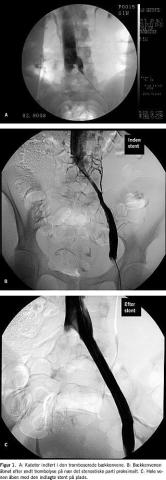

Den akutte behandling ved DVT sigter mod at nedsætte risikoen for lungeemboli, hvilket meget effektivt gøres med heparin. På længere sigt får 50% af patienterne med DVT imidlertid svære symptomer på kronisk venøs insufficiens, primært pga. destruerede veneklapper. Lokal trombolyse, givet via et kateter placeret i selve tromben indført fra en perifer vene, kan opløse de fleste friske tromber (< 14 dage). Behandlingen har indtil nu næsten udelukkende drejet sig om femoro-iliakal trombosering. Herved genskabes det venøse afløb, men vigtigere er det, at veneklapfunktionen ser ud til at bevares også på længere sigt. Når trombosen er opløst, viser der sig hos flertallet en stenose typisk ved indløbet af v. iliaca

i v. cava inferior (altid på venstre side), som dilateres og stentbehandles (Figur 1 ). Den tekniske succesrate, hvad angår opløsning af tromben og stentbehandlingen, angives at være på 90% eller derover, og omkring 60-90% er åbne efter et år [1]. Vor egen erfaring ved femoro-iliakal DVT er mindst lige så god efter behandling af de første 40 patienter.